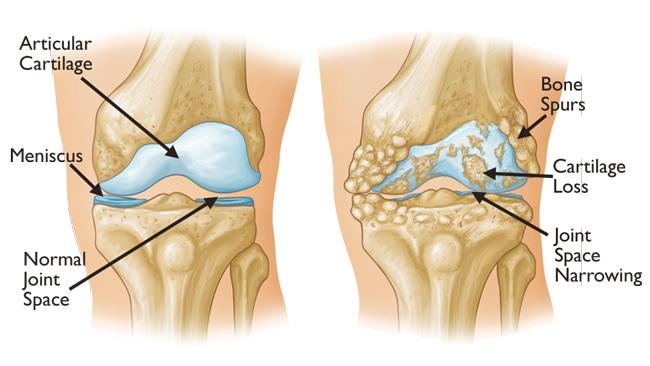

Arthritic diseases include rheumatoid arthritis and psoriatic arthritis, which are autoimmune diseases; septic arthritis, caused by joint infection; and the more common osteoarthritis, or degenerative joint disease. Arthritis can be caused from strains and injuries caused by repetitive motion, sports, overexertion, and falls. Unlike the autoimmune diseases, osteoarthritis largely affects older people and results from the degeneration of joint cartilage. Other forms are discussed below.

Nearly a quarter of people over the age of 40 experience painful osteoarthritis, making it a leading cause of disability in adults. Osteoarthritis degrades joint-cushioning cartilage, and there is currently no way of reversing this damage: the only option is to manage pain with medication, and eventually, joint replacement.

The body is pretty good at repairing itself, but some parts of our anatomy struggle to bounce back after an injury. One such material is cartilage - the spongy yet firm connective tissue that keeps our bones from rubbing and jarring against each other. Over time, the translucent or 'hyaline' components of cartilage can become heavily degraded, resulting in painful conditions like osteoarthritis and chondromalacia. Scientists have been working on a way to regenerate hyaline cartilage for years, and now a team led by Northwestern University in the US has achieved a breakthrough. They have developed a biomaterial that, injected into damaged cartilage in living sheep, acted as a scaffold that promoted cartilage regrowth in active joints.